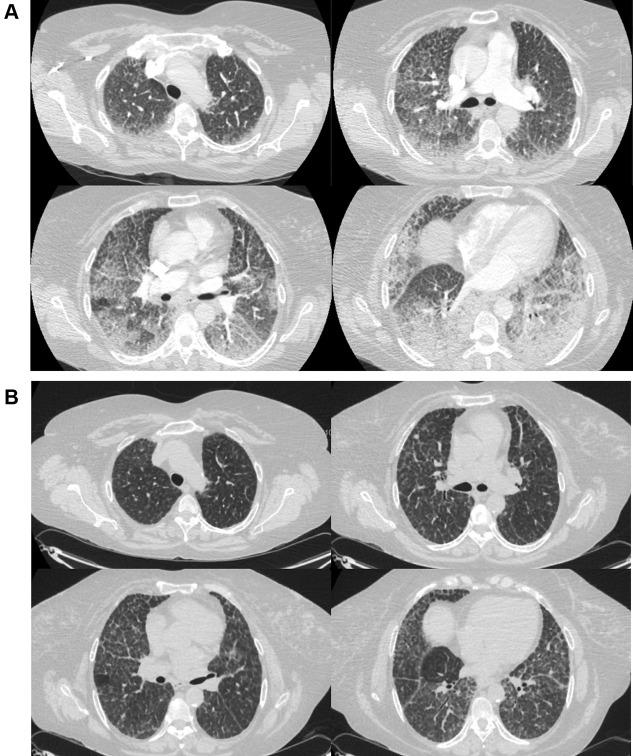

A 51-year-old Puerto Rican woman, with a known but inconclusive diagnosis of interstitial lung disease (ILD) since 2002 and recent moderate COVID-19, is now presenting with subacute worsening dyspnea on exertion. The patient had sporadic medical care over the years for her ILD (Table 1). Prior workup included chest CT imaging with a "crazy-paving" pattern of lung disease, as defined by ground-glass opacity with superimposed interlobular septal thickening and visible intralobular lines. Bronchoscopy showed normal airway examination, and BAL revealed clear fluid with foamy macrophages and negative cultures. Video-assisted thoracoscopic surgery and transbronchial biopsy specimens both showed foamy macrophages. Results of pulmonary function testing (PFT) revealed an isolated gas transfer defect on diffusing capacity of the lungs for carbon monoxide (Dlco). She had lived with mild yet nonprogressive functional impairment and stable exercise intolerance over these years. She was then hospitalized for COVID-19 in August 2020 and for recurrent shortness of breath in September 2020. She now presented 4 months following her September 2020 hospitalization.

一位 51 岁的波多黎各女性,自 2002 年以来已知但不确定的间质性肺病(ILD)诊断,以及最近中度 COVID-19,现在出现亚急性进行性呼吸困难。患者多年来一直间歇性地接受 ILD 的医疗护理(表 1)。之前的检查包括胸部 CT 成像,呈现出“铺路石样”的肺部疾病模式,定义为磨玻璃影伴小叶间隔增厚和可见小叶内线。支气管镜检查显示气道正常,BAL 显示澄清液体,含有泡沫状巨噬细胞,培养结果为阴性。胸腔镜手术和经支气管活检标本均显示泡沫状巨噬细胞。肺功能检查(PFT)结果显示一氧化碳弥散量(Dlco)的肺部气体转移缺陷孤立。多年来,她一直患有轻度但无进展的功能障碍和稳定的运动不耐受。然后,她于 2020 年 8 月因 COVID-19 住院,并于 2020 年 9 月因反复呼吸急促再次住院。现在,她是在 2020 年 9 月出院后 4 个月出现的。